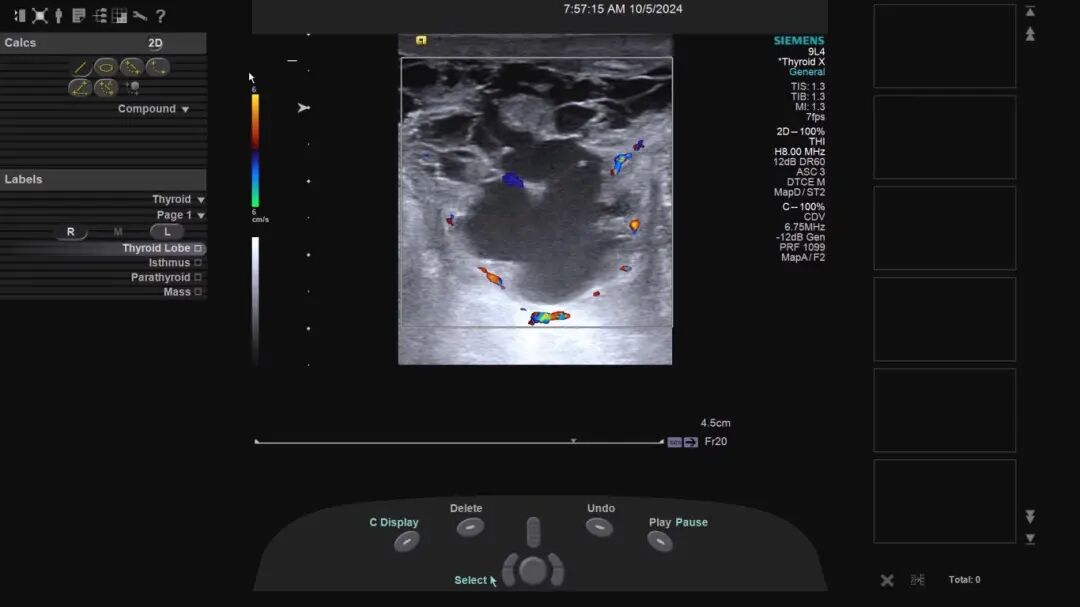

坐骨结节滑囊炎超声上表现为坐骨结节浅面无回声或混合回声包块,边界较清楚,形态不规则,可为椭圆形、扁平状或不规则形,加压肿块可变形,囊壁较厚,内壁多不光滑,内可为透声较好的无回声或细小的点状回声,少部分囊腔内可见絮状或团状高回声,大多数囊腔呈多房状。

急性期囊壁或分隔光带上可见丰富的血流信号,慢性滑囊炎时血流信号程度不等。这种情况,非常适合使用超声引导下穿刺进行积液的抽吸,该技术具有微创、精准、可视、低耗、高效、便捷的特点,能够减轻患者日常生活的痛苦与不便。